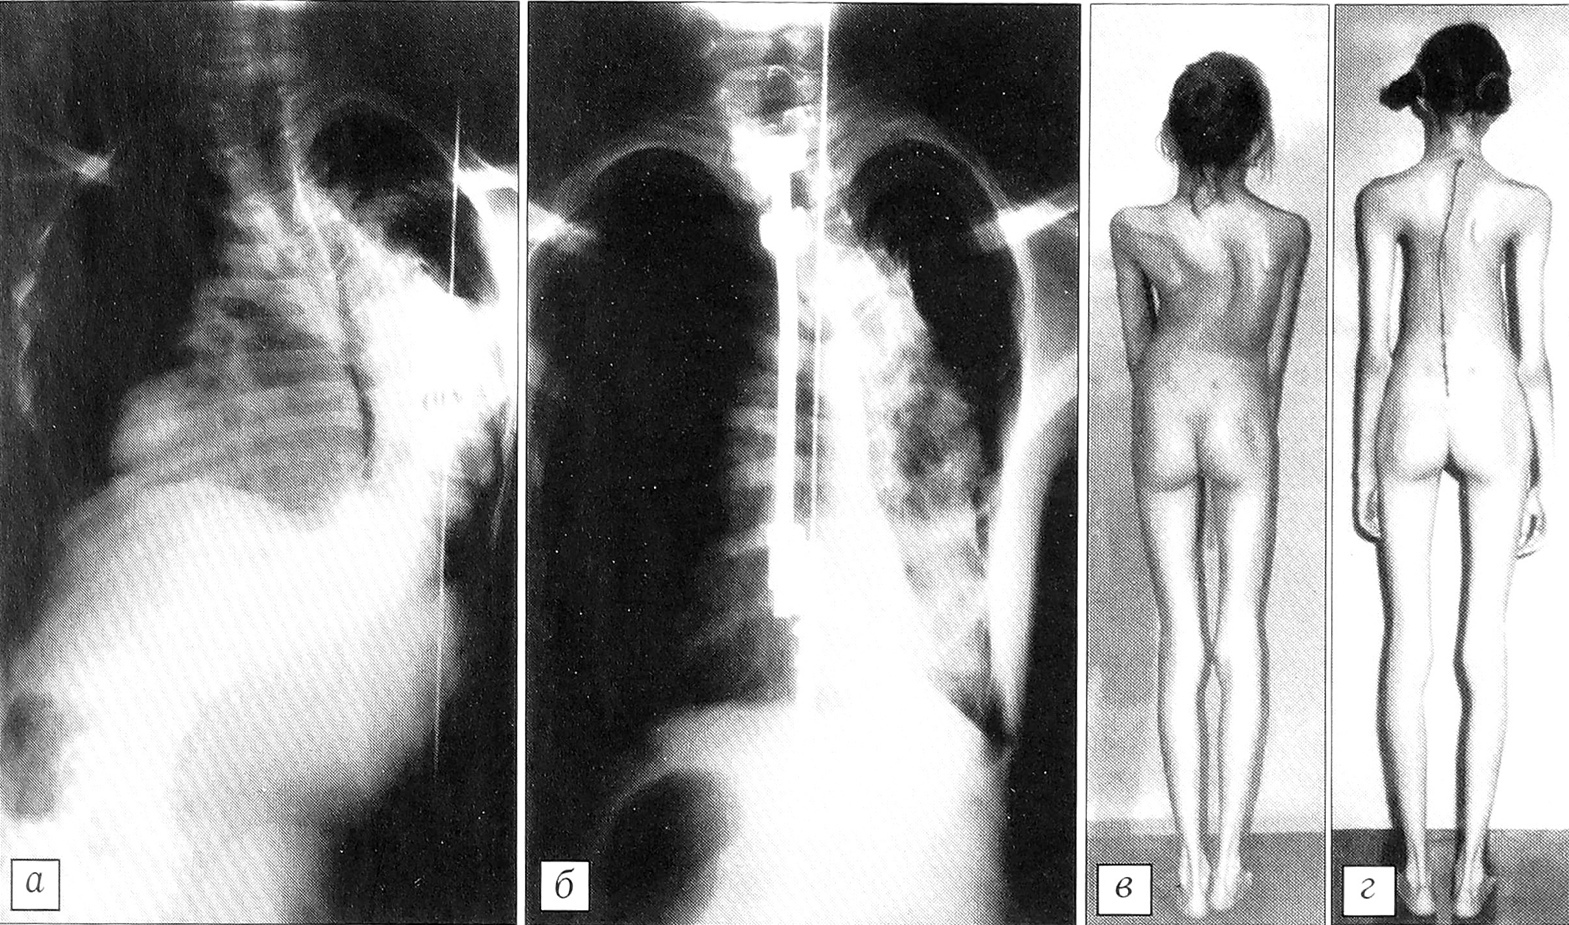

Больная Ш. 12 лет. Синдром Марфана, правосторонний грудной сколиоз 108°. a — рентгенограмма позвоночника до начала лечения; б — после многоэтапного оперативного лечения в течение 3 лет: величина деформации после переднебокового эпифизеоспондилодеза и коррекции инструментарием CD уменьшена до 64°; после двух этапных коррекций и завершающего дорсального спондилодеза с дополнительным использованием проволочных петель по Drummond величина дуги 60°; в — внешний вид больной до лечения, г — после лечения. Рост девочки до начала лечения 141 см, по его окончании — 159 см.

При обсуждении методов хирургического лечения детей с применением металлоимплантатов постоянно встает вопрос о нежелательном влиянии последних на рост пациентов. Само по себе это опасение вполне оправданно, но лишь в тех случаях, когда оперативное лечение состоит в одноэтапном вмешательстве. Используемая нами методика многоэтапного лечения имеет целью, помимо всего прочего, сохранить потенции роста позвонков на вогнутой стороне деформации и тем самым не ограничить рост туловища больного. Полученные результаты подтверждают правильность наших предположений. У детей, находящихся в процессе лечения, среднегодовой прирост составляет 7,6 см, а у завершивших лечение — 6,2 см в год (см. рисунок, в, г). Некоторая разница, вероятно, объясняется тем, что дети, закончившие лечение, начали его несколько позднее остальных.